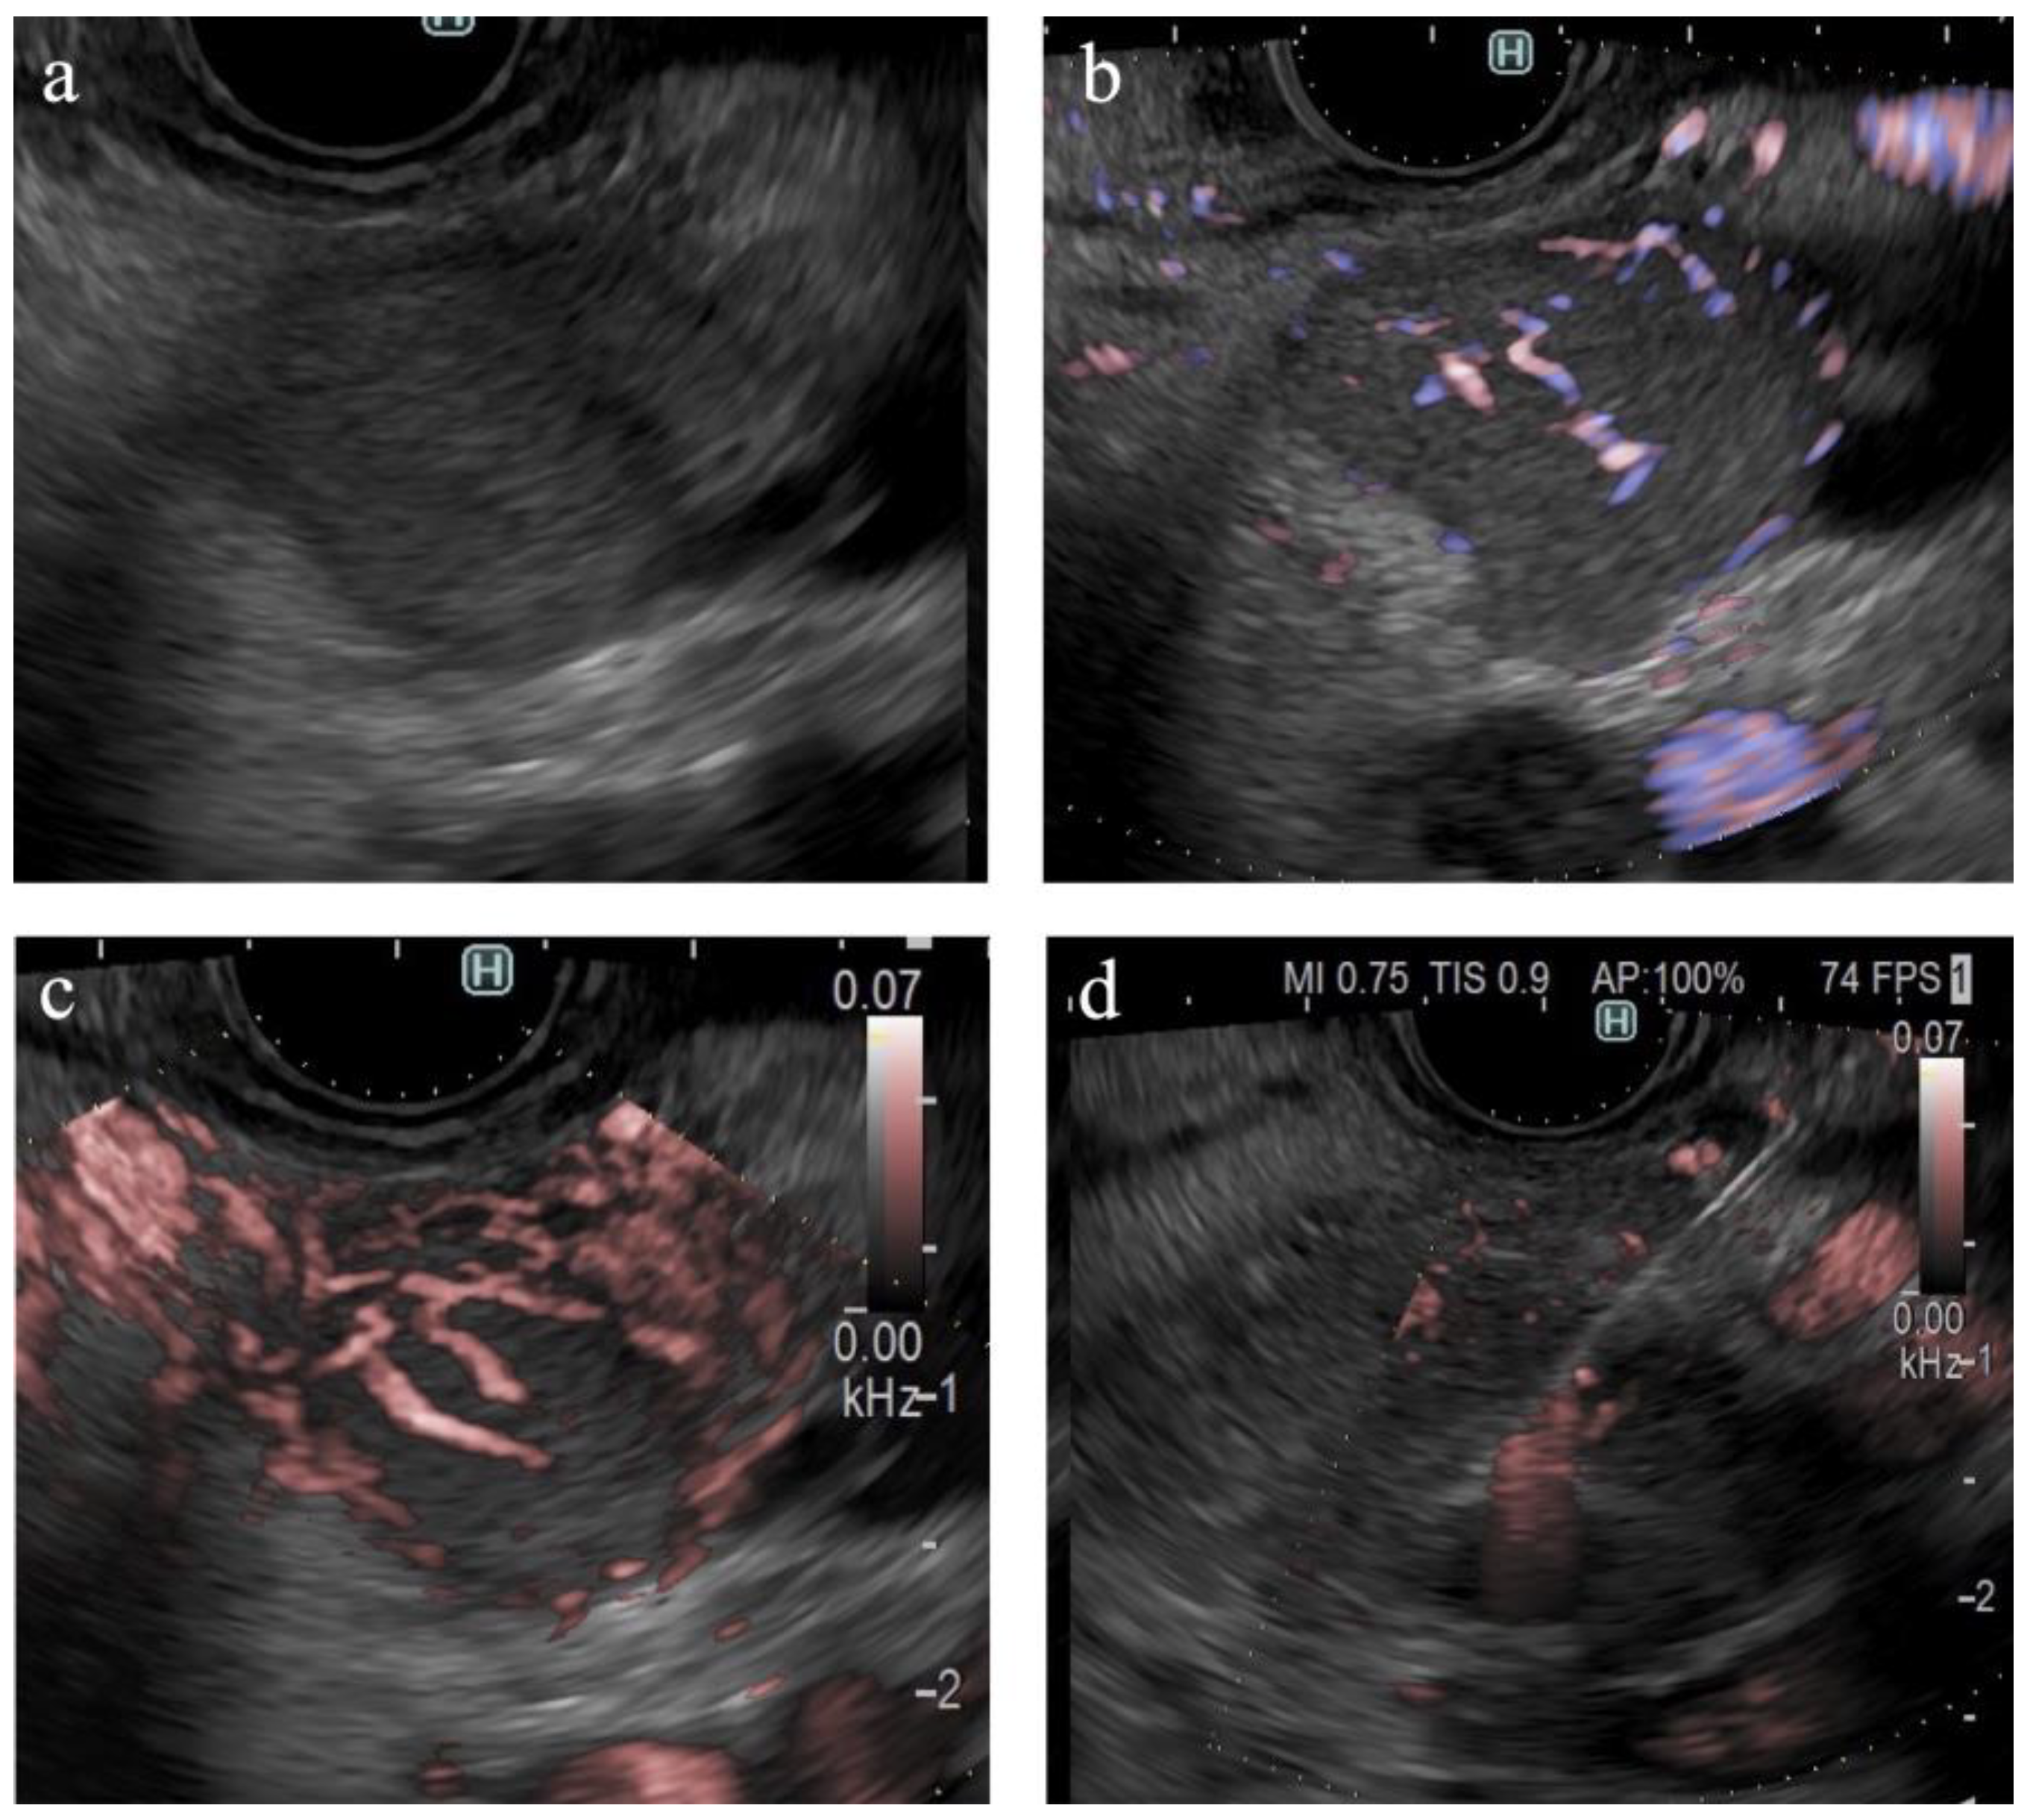

Figure 4.

Vessel images of DFI. (a) Pancreatic cancer; (b) mass-forming pancreatitis; (c) neuroendocrine neoplasm; and (d) metastatic tumor (renal cell carcinoma). The arrowheads in each figure show the margin of the SPLs.

Table 2 presents the result of the univariate analysis of the characteristics and findings of pancreatic cancer and other lesions. Pancreatic cancer was observed significantly more frequently in the pancreatic head (54%, p = 0.013) and in areas deeper than 25 mm (63%, p = 0.042). The number of large SPLs (>20 mm) was greater in patients with pancreatic cancer than in other types of pancreatic lesions; however, the difference was not statistically significant. The majority of lesions were classified as hypoechoic lesions on B-mode (98% (102/104), p = 0.473). The borders were “well-defined” in 70% of the pancreatic cancer lesions and 81% of other types of lesions (p = 0.362). “Irregular contour” and “heterogenic internal echo” were observed in 88% (73/83) and 83% (69/83) of pancreatic cancer lesions, respectively (p < 0.01). eFLOW detected the presence of vessels in 27% (28/104) of lesions only. The shape and distribution of the vessels were classified in cases where vessels were present within the lesion; however, no significant differences were observed. DFI detected the presence of vessels in 96% (100/104) of the lesions. Thus, the detection rate of DFI was significantly higher than that of eFLOW (p < 0.01). Four lesions without vessels were classified as “hypovascular”. Hypovascular lesions were significantly more frequent in patients with pancreatic cancer (p < 0.01). The distribution and shape of the vessels were evaluated in 100 cases wherein the vessels were present within the lesions. Peritumoral and spotty vessels were significantly more frequent in pancreatic cancer lesions (84% [66/79] and 86% [68/79], respectively; Figure 4a) than in other types of lesions (38% [8/21] and 43% [9/21], respectively; p < 0.01).

3.6. Findings on Lesions Other Than Pancreatic Cancer

Table 4 presents the findings in the NEN (n = 6) and MFP (n = 9) groups. No significant differences were observed between the two groups in terms of lesion characteristics. All lesions were hypoechoic on B-mode. No significant differences were observed between the B-mode and eFLOW findings. DFI could visualize vessels within the SPLs in all lesions. Notably, 83% (5/6) of the NEN lesions were hypervascular, whereas all MFP lesions were hypovascular (Figure 4b), with a statistically significant difference (p < 0.01).

The findings of this study demonstrate the utility of DFI for purposes other than the differential diagnosis of SPLs. DFI enabled the identification of small hypervascular lesions within 10 mm, which was unexpected (Figure 4c,d). The frame rate of DFI is higher than those of B-mode and eFLOW; thus, DFI can be used as a screening evaluation for patients with Multiple Endocrine Neoplasia type 1 or von Hippel–Lindau disease [41,42]. Hypersensitivity to vascular structures aided the avoidance of thick vessels during the EUS-FNB procedure (Figure 5). DFI, rather than eFLOW, can be used to define the vessels more precisely in patients with NEN. This technique enables the effective acquisition of tissue samples without major bleeding. The absence of linear vessels in pancreatic cancer lesions can aid the detection of tumor margins (Figure 6). A pancreatic cancer lesion without a detectable margin was observed on B-mode and eFLOW in this case, and the initial EUS-FNB result was a false negative. Subsequently, DFI was performed, and the normal vessels in the surrounding pancreatic parenchyma near the tumor margin disappeared. The diagnosis was confirmed by puncturing the areas without vessels on DFI. Thus, DFI can be considered a novel tool for determining the differential diagnosis of pancreatic cancer in the future.